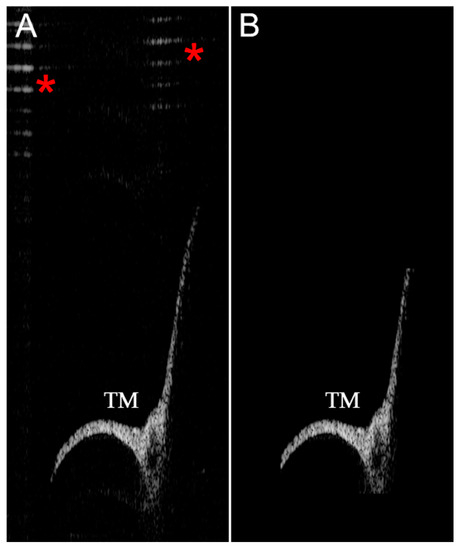

2.3. Large Object Detection Algorithm

2.4. Small Object Detection Algorithm

2.5. Image Recognition Algorithms